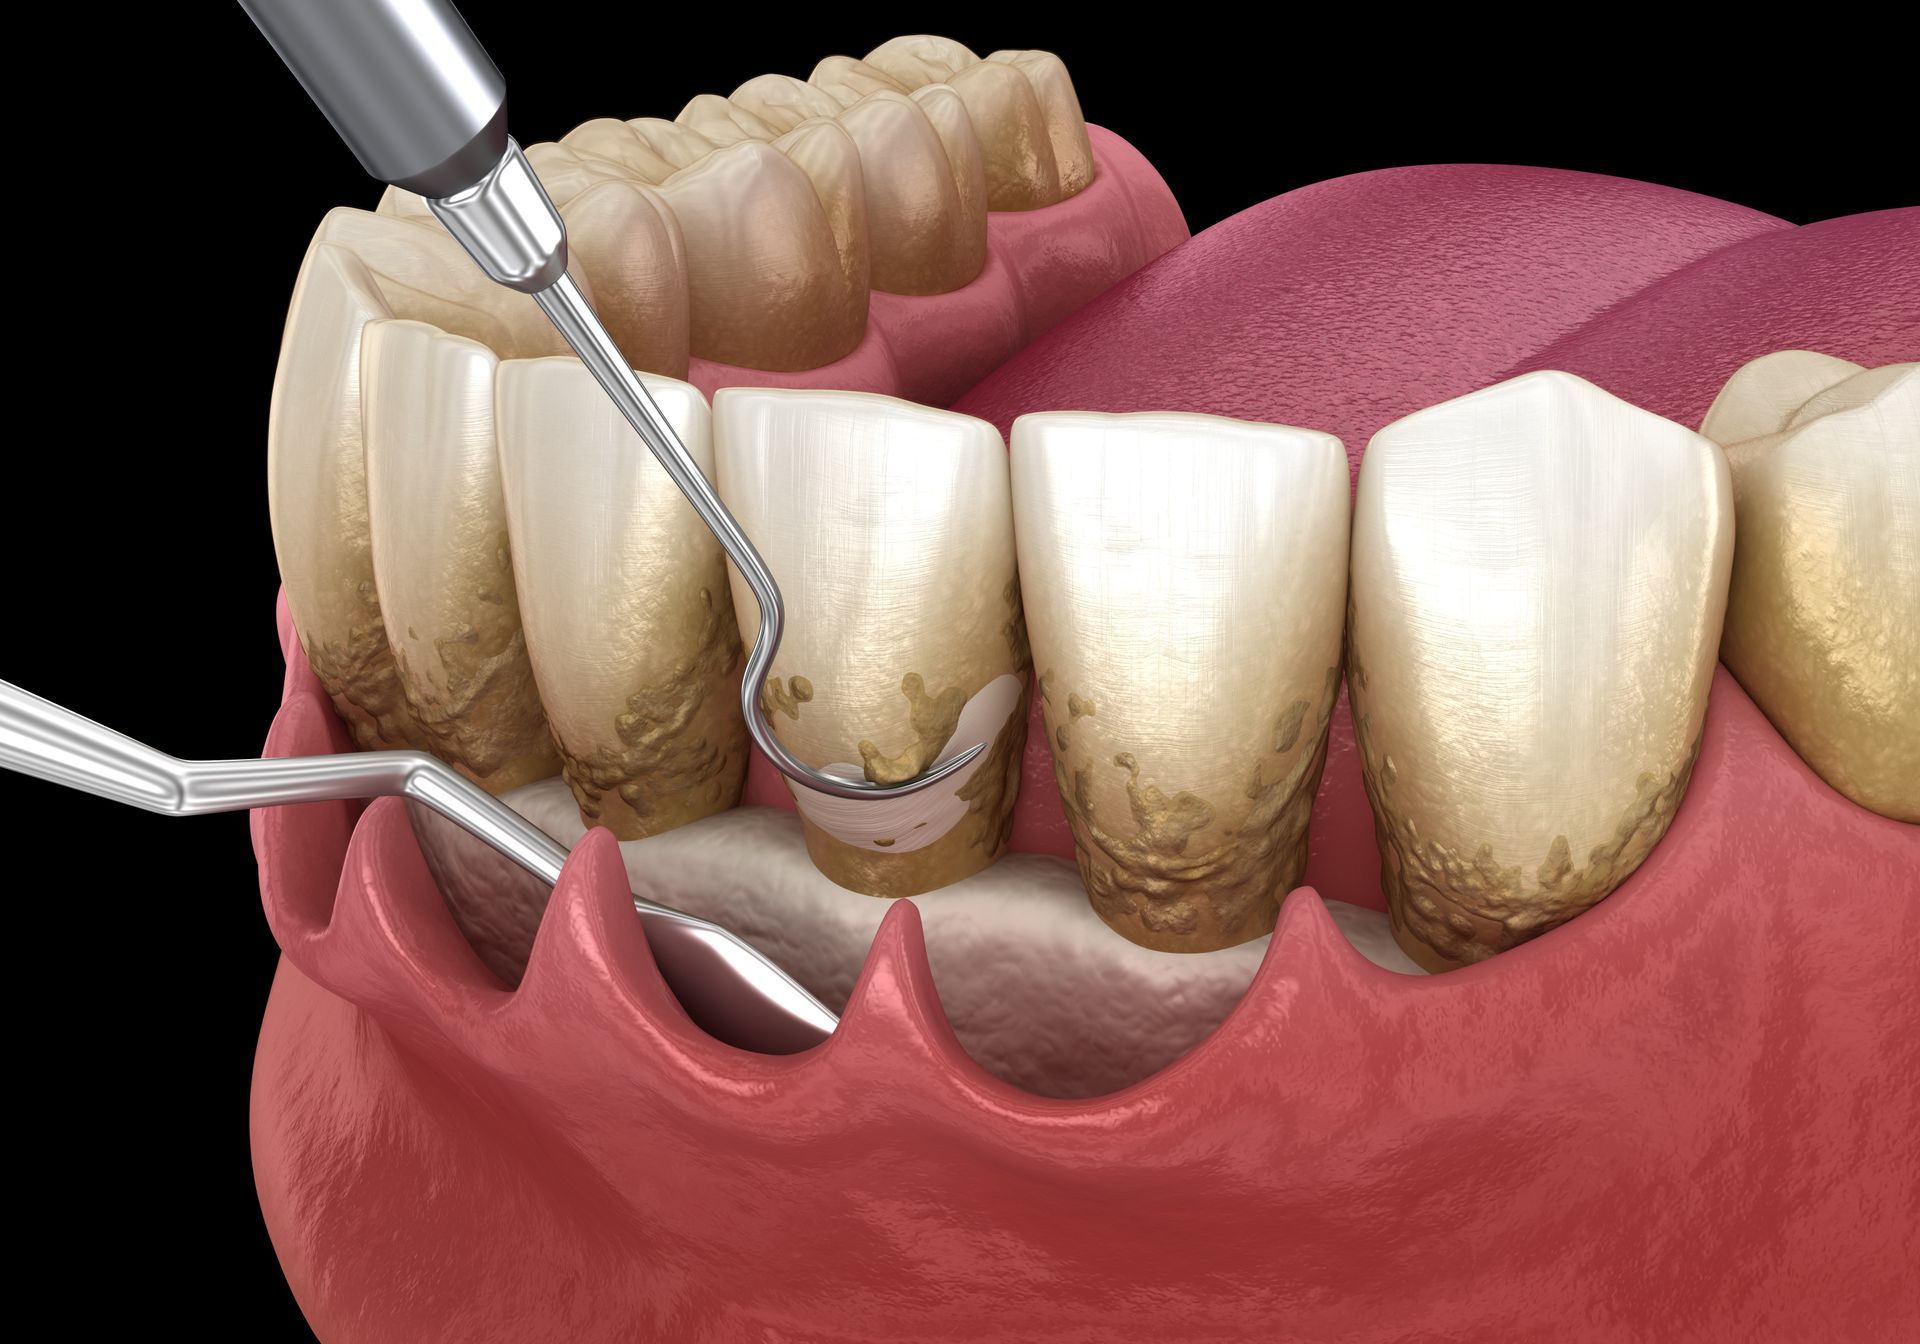

- Professional deep cleanings (scaling and root planning)

- Removal of plaque and tartar below the gumline

The goal of treatment is to eliminate infection, reduce inflammation, and stabilize the supporting structures of the teeth.